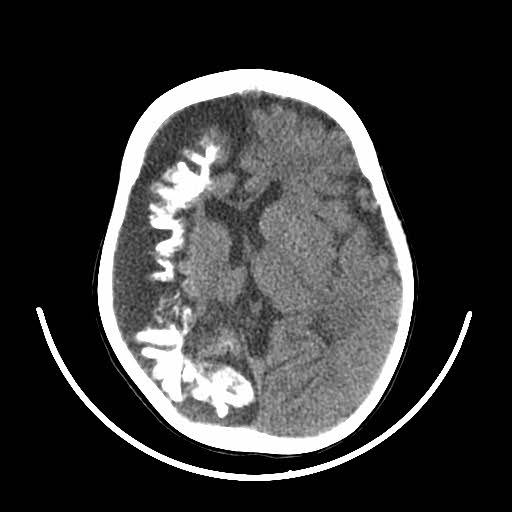

What's the Diagnosis?